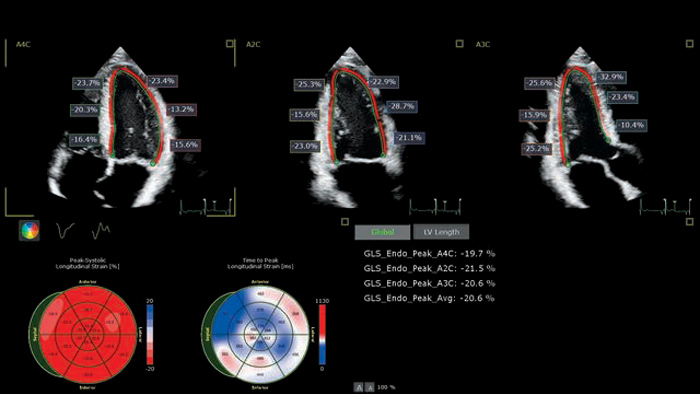

The EPIQ CVx is a dedicated cardiac ultrasound solution which brings significant advancements in functionality. This helps you deliver better care through higher processing power, exceptional imaging with more clarity & sharpness, improved exam efficiencies, complemented by the proven, robust quantification capabilities of Ultrasound Workspace.